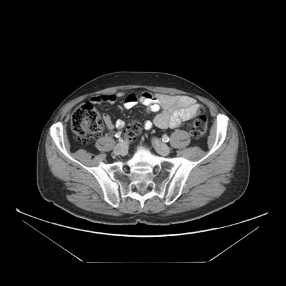

4. RIFE를 이용한 Image Interpolation(CT 이미지)

http://www.castlemountain.dk/atlas/index.php?page=mulrecon에서 다운로드 하였습니다.(JPEG파일)

http://castlemountain.dk/mulrecon/abdomenBladderCancerCT.zip : 다운로드 주소

입력 이미지로 다음의 이미지를 삽입하였습니다.

출력 결과 위의 두 이미지 사이에 밑의 3이미지가 추가로 생성되었습니다.